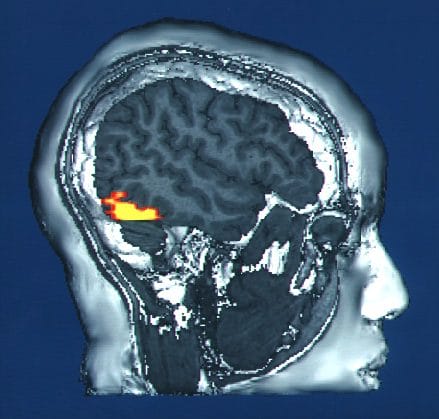

MRI of the visual cortex area responsible for facial recognition

What is so intellectually tantalizing about Donna’s deficit is the extraordinary specificity of her trouble, present from birth; nothing else appears to be wrong with her cognitive faculties. It may also be argued that faces are quite special to the human perceptual systems. Recent brain-scanning techniques have yielded enormous insight into how the human mind perceives and analyzes face information, such as the 1997 discovery of a specific face-processing area of the cortex (the “fusiform face area”) or the neurologic interpretation of autism as a maldevelopment in the brain hardware that naturally attracts one’s attention to a face. And as referenced earlier, the existence of “super-recognizers” implies that the ability to remember a face may be more of a spectrum, ranging from the elite to the unable.